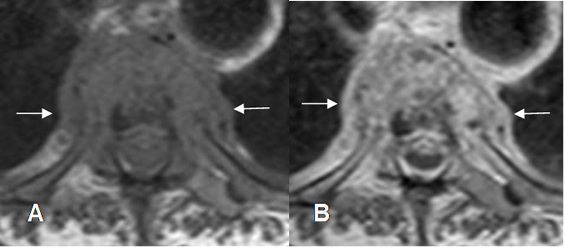

Otro signo característico de la espondilodisquitis, es la extensión paraespinal y epidural, de los cambios inflamatorios. La ausencia de estos hallazgos, excluyen la infección. (31, 57). (Fig 140 A y B).

Fig 140 A. Espondilodisquitis.

A: RM axial en T1 y B: RM axial en T1 con contraste. Alteración en la señal del disco por proceso infeccioso, con masa de tejidos blandos, que realzan con el contraste.

Fig 140 B. Espondilodisquitis.

A: RM sagital en T1. Alteración en la señal del disco y las placas terminales, con masa de tejidos blandos que ocupa el canal.

B: RM sagital y C: RM axial en T1 con contraste. Realce oseo y de la masa de tejidos blandos, de forma homogénea, que corresponde a flemón y ocupa el espacio epidural.